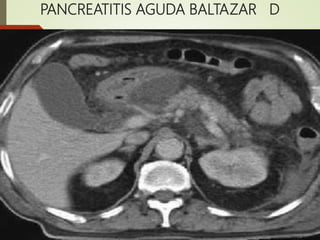

Colección

33-50% 4

PANCREATITIS AGUDA BALTAZAR D

TÉCNICAS DE IMAGEN oRadiografia simples(Descarta afecciones quirúrgicas abdominales) o Ecografia Abdominal(Para identificación de litiasis biliar) oTomógrafo Computadorizado(TC) o Criterios radiológico de gravedad de Balthazar El sistema desarrollado por Balthazar valora La extensión de la necrosis pancreática y presencia de lesiones extrapancreáticas en niveles de puntuación de 0-10, en que la puntuación 7-10 se asocia com mayor mortalidad 17% y morbilidad 92%

Panc. Grado PtsDescripción morfológica Necrosis Pts PAL A O Páncreas normal O% O PAL B 1 Aumento focal o difuso de páncreas O% O ?? C 2 B+ Inflamación Peri- Pancreática <33% 2 PAG D 3 C+ Colección líquida única 33-50% 4 PAG E 4 D+ dos colecciones líquidas y gás 50% 6